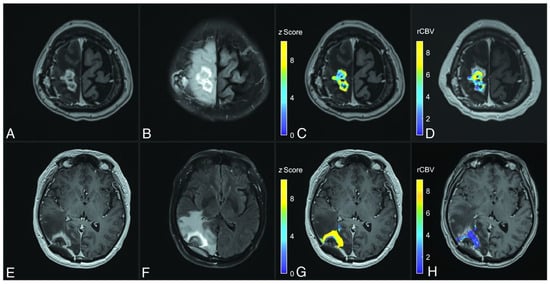

4.3. Contrast-Enhanced T2-FLAIR: A New Imaging Biomarker

The existing AI models designed to distinguish RN from TP utilize multiparametric MRI data acquired from standard brain tumor protocols, which commonly encompass diffusion-weighted imaging (DWI), pre-contrast T1, T2, T2-FLAIR, and post-contrast T1 [120]. Exploring new imaging sequences and techniques for integration into these protocols represents a promising avenue for improving AI model performance. Contrast-enhanced T2-FLAIR (T2FLAIRc) has shown the potential to provide additional diagnostic information. At our institution, T2FLAIRc is routinely acquired alongside pre-contrast T2-FLAIR, primarily to enhance the detection of leptomeningeal disease [121]. Recent investigations have demonstrated that the standardized T2FLAIRc signal intensity is significantly elevated in RN compared to TP, suggesting its utility as a novel imaging biomarker (Figure 4) [122]. Furthermore, a univariable analysis using standardized T2FLAIRc achieved a sensitivity of 75% and a specificity of 86% in differentiating RN from TP. Based on these promising results, we hypothesize that AI models incorporating T2FLAIRc within mpMRI protocols will demonstrate superior performance compared to univariable models. Furthermore, T2FLAIRc should serve as a valuable parameter for augmenting the capabilities of deep learning (DL) models.

Figure 4.

T2FLAIR post-contrast (T2FLAIRc) z score parameter maps for cases of tumor progression (top row, A–D) and radiation necrosis (bottom row, E-H). (A,E) Axial T1-weighted MPRAGE post-contrast imaging; (B,F) T2FLAIRc imaging; (C,G) T2FLAIRc z score for enhancing tumor voxels overlaid on T1-weighted post-contrast images; (D,H) the relative cerebral blood volume (rCBV) map from follow-up dynamic susceptibility perfusion MRI. The case of tumor progression shows lower T2FLAIRc z values (mean, 5.8 [standard deviation 2.0]) than radiation necrosis (mean, 12.6 [SD 5.7]). The rCBV values are higher in tumor progression (mean, 4.8 [SD 2.3]) compared to radiation necrosis (mean, 1.3 [SD 1.2]). Figure was reproduced from Heyn et al. with permission from the publisher [122].